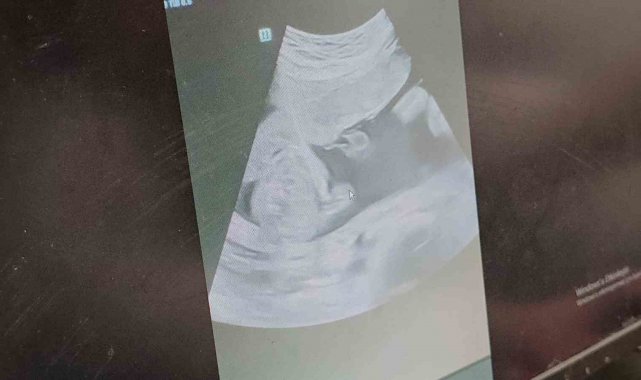

Batman'da, Türkiye'de ender görülen tıbbi müdahalelerden 10'ncusu yapıldı. İkiz kardeşini ve annesini zehirlemek üzere olan ikizlere anne karnında mikrodalga yöntemi ile yapılan müdahale sonucu anne ve çocuklardan biri sağlığına kavuştu. Doğum gerçekleşene kadar ölen ve yaşayan kardeşler birlikte kalacak.

İkiz bebeklere 27 haftalık hamile olan anne adayı Büşra Güneş, rutin kontrolleri için gittiği Batman Eğitim ve Araştırma Hastanesinde ikizlerden birinde gelişim geriliği olduğu belirlendi. Aynı hastanedeki Perinatoloji(riskli gebelik) Yan Dal Uzmanı Uzman Doktor Bülent Babaoğlu'na yönlendirilen anneye yapılan tetkiklerde ikizlerden birinin 1 kilogram iken diğerinin 350 gram olarak ölçüldü, bunun üzerine aile il dışına sevk edildi.

Ailenin kararı üzerine Türkiye'de bugüne kadar görülen 10'uncu vaka olan anneye mikrodalga ile anne karnına girilerek gelişim geriliği ve kalp atışı durma noktasına gelen ikiz bebeğe giden kordonlar tıkatılarak kan akışı kesildi. Böylece hem anne hem ikizlerden biri sağlığına kavuşmuş oldu. İlk kez anne-baba olacak olmanın heyecanını yaşayan anne Büşra ve baba İslam Güneş, çocuklarını kucaklarına alacakları günü sabırsızlıkla bekliyor.

Bu yoğunluğa rağmen Türkiye'de ender görülen müdahaleleri de gerçekleştirdiklerini belirten Babaoğlu, "Bu süreçte yaptığımız bazı girişimsel müdahaleler de oluyor. Bunlarda biri tek yumurta ikizi monokoryonik bir gebede bebeklerden birisi 1 kilogram iken diğeri 350 gramdı yani gelişme geriliği vardı. Takiplerde gelişme geriliği olan bebeğe anneden giden kan akımlarının azaldığı ve geriye gittiği yani o bebeği kaybetmek üzere olduğumuzu tıbbi bilgiler eşliğinde tanısını koyduk. Bu süreçte ya hiçbir şey yapmadan diğer bebeğin de etkilenmesini bekleyecektik ya da etkilenmiş olan zaten kalp atışlarının durmasını beklediğimiz bebeğe anne karnında bir müdahale ile diğer bebeği yaşatmayı yani gebeliğin devamını sağlamayı planladık" dedi.

Doktor Babaoğlu, gerekli hazırlıkların ardından mikrodalga ile anne karnına girildiğini aktarak, "Yapılan müdahale ile hem anne hem de ikizlerden biri sağlığına kavuştu. Nihayetinde müdahaleyi yaptık. Mikrodalga yöntemiyle kalp atışları sonlanmak üzere olan bebeğin vücuduna gelen kordonu lazer yöntemiyle tıkadık. Bundaki amaç, o bebekten ortak beslenme olan kanala vefat ettikten sonra ya da olumsuz etkilendikten sonra zehir ya da olumsuz akımın oraya geçmesini engellemekti. Müdahalemiz başarılı oldu. Şu an için kontrollerimizde anne de bebekte sağlıklı. İnşallah gebeliğe devam edeceğiz bu şekilde" diye konuştu.